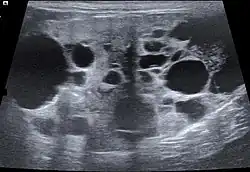

Die Ultraschalluntersuchung gestattet es, morphologische Veränderungen der Nieren detaillierter darzustellen. Neben Größen- und Formveränderungen lassen sich auch Nierenzysten, örtlich abgegrenzte (fokale) Organschäden, Wassersacknieren und Harnstauungen sowie Tumoren darstellen. Kaum abgegrenzte (diffuse) Organveränderungen gehen zwar mit Änderungen der Echogenität einher, sind aber nur selten definierten Erkrankungen zuzuordnen.[22] Mittels „Pulsed-Wave-Doppler“ lassen sich auch Durchblutungsstörungen nachweisen.[23] Häufig kommt es bei der chronischen Nierenerkrankung auch zu Verkalkungen (Nephrokalzinose), die sich ebenfalls sonografisch nachweisen lässt.[24]